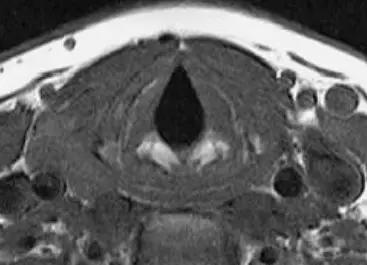

3、MRI

- 采用颈部线圈,下颌上抬,垫高肩部以抬高喉部;

- 横断面扫描与声带平行,扫描范围自会厌上缘至环状软骨下缘,层厚3-5mm;

- 冠状面显示声带、室带、喉室、胸廓入口等情况较好;

2、CT、MRI检查

正常喉部CT